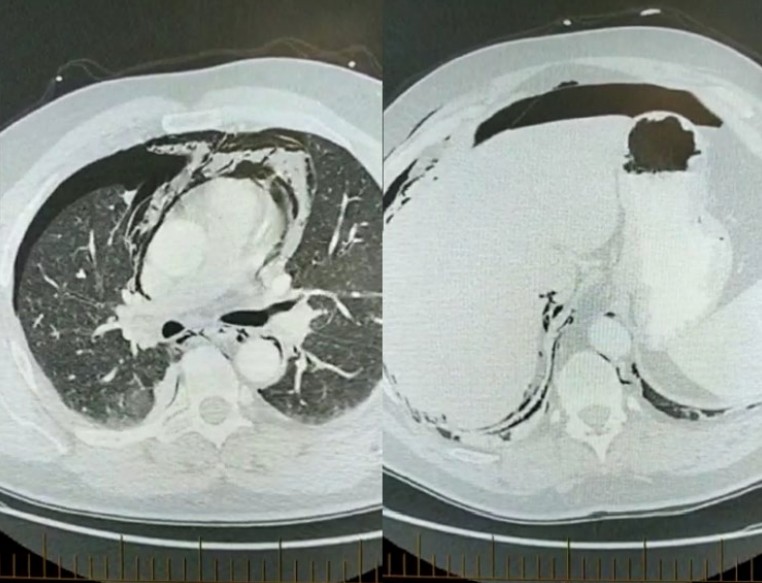

Fever and pain post scopes

A 52-year-old man presents to your district hospital at 2000h with SOB, abdominal pain and fever. He has had an …